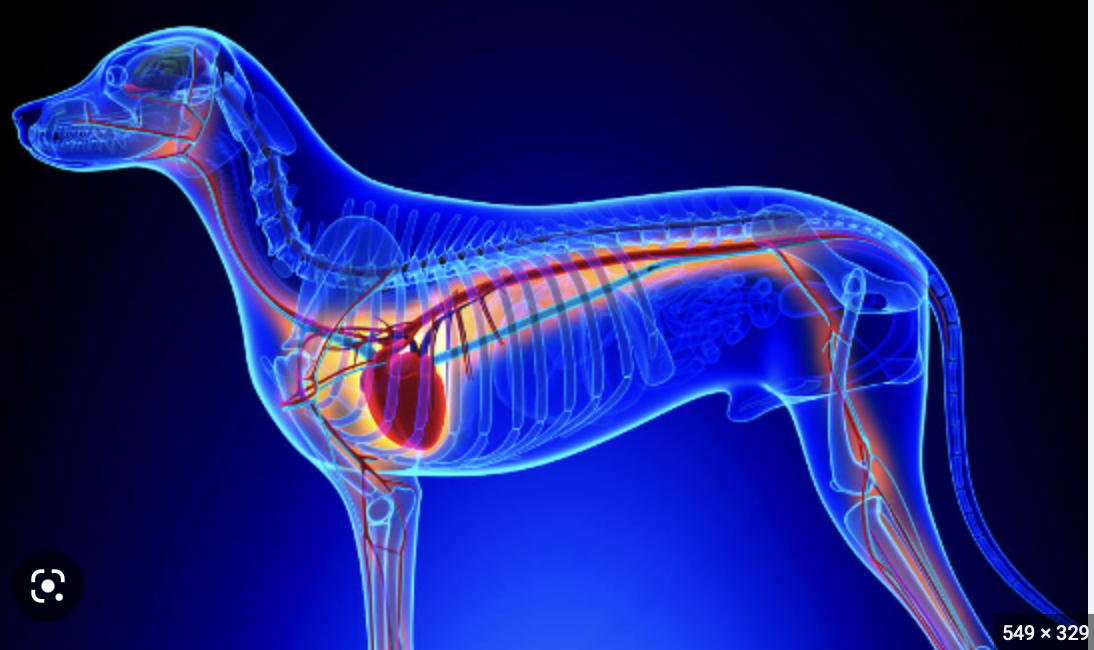

심장은 인간의 몸에서 특정한 위치에 자리잡고 있으며, 그 구조와 기능에 따라 여러 중요한 역할을 수행합니다. 심장은 흉강 중앙에 위치해 있으며, 두 개의 폐 사이에 자리잡고 있는 '가슴뼈'(sternum)와 가까운 위치에 있습니다. 즉, 심장은 왼쪽으로 살짝 치우친 형태로, 아래쪽은 횡격막(diaphragm)이라는 근육에 의해 지지받고 있습니다. 이러한 구조는 심장이 외부 압력으로부터 보호받을 수 있도록 도와줍니다.

심장은 네 개의 주요 구역으로 나뉘며, 각각의 구역은 특정한 혈액 순환 기능을 맡고 있습니다. 이 네 개의 구역은 우심방(right atrium), 우심실(right ventricle), 좌심방(left atrium), 좌심실(left ventricle)로 구성됩니다. 이들 각 구역은 서로 다른 기능을 하며, 신체의 혈액 흐름을 조절합니다.